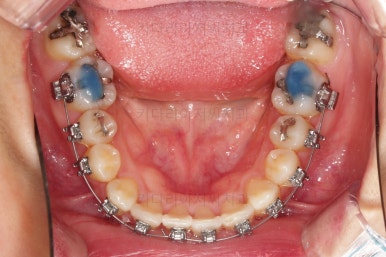

장치를 구성합니다.

이번 환자분은 윗니는 세라믹, 아랫니는 메탈 장치를 선택하셨는데요.

둘 다 물론 자가결찰 장치였고요.

동일한 제품의 장치이므로 혼용해서 쓰는게 가능합니다.

많이 보이는 부분은 세라믹, 잘 안보인다고 여겨지시는 부분은 메탈로 선택하면서 치료비 측면도 함께 고려한거죠.

장치 부착 직후의 모습인데요.

아랫니는 발치 없이 가지런하게 해주고요.

윗니는 가지런하게 한 뒤 발치공간을 서서히 닫아줍니다.

유치는 크기가 작았기 때문에 생각보다 빨리 공간이 닫히고 있고요.

반대쪽 작은 어금니 부분은 공간이 아직 많이 남은 편이죠.